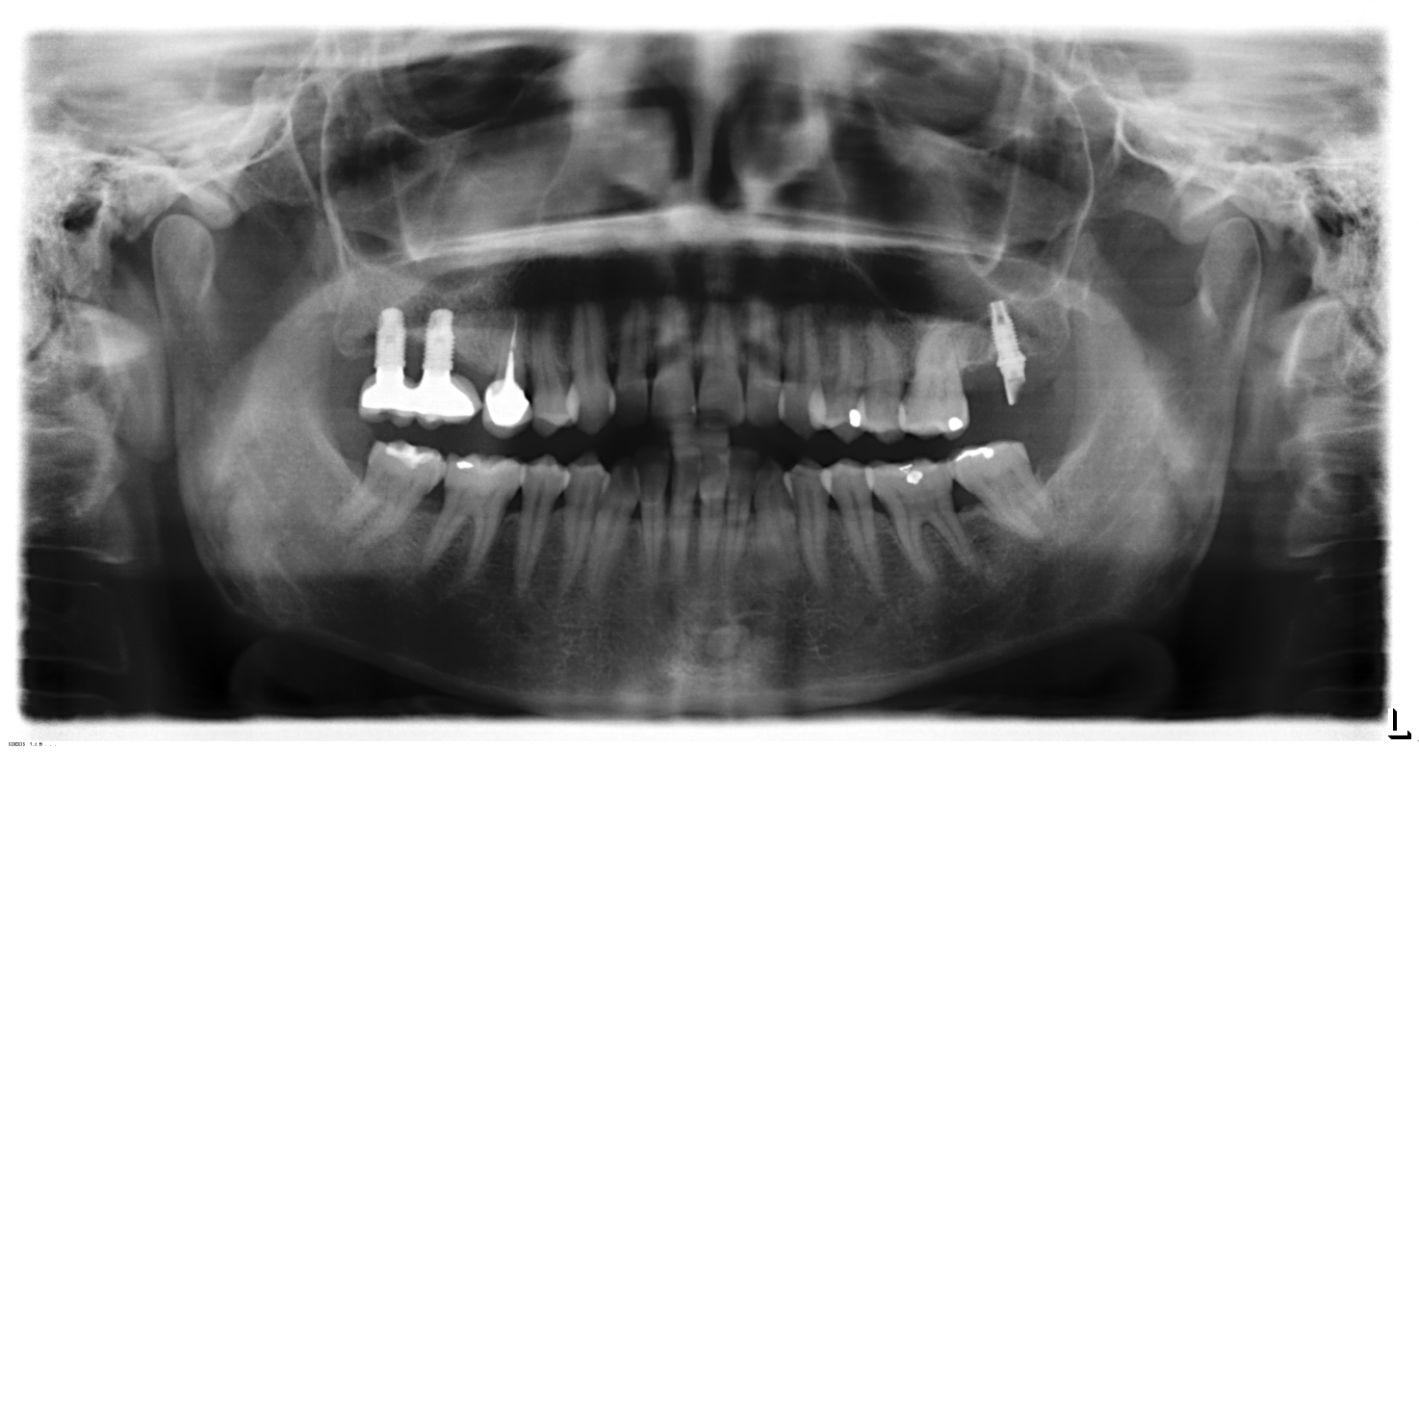

Buenas, paciente acude a consulta con prótesis sobre implante removible totalmente desajustada, necesito identificar marca de implantes y Locator. Los implantes tienen periimplantitis. Gracias.

Hola buenas tardes, necesitamos saber que implante es el de la pieza 27. Para poder colocar la corona.

Tengo que rehabilitar estos implantes. Muchas gracias de antemano